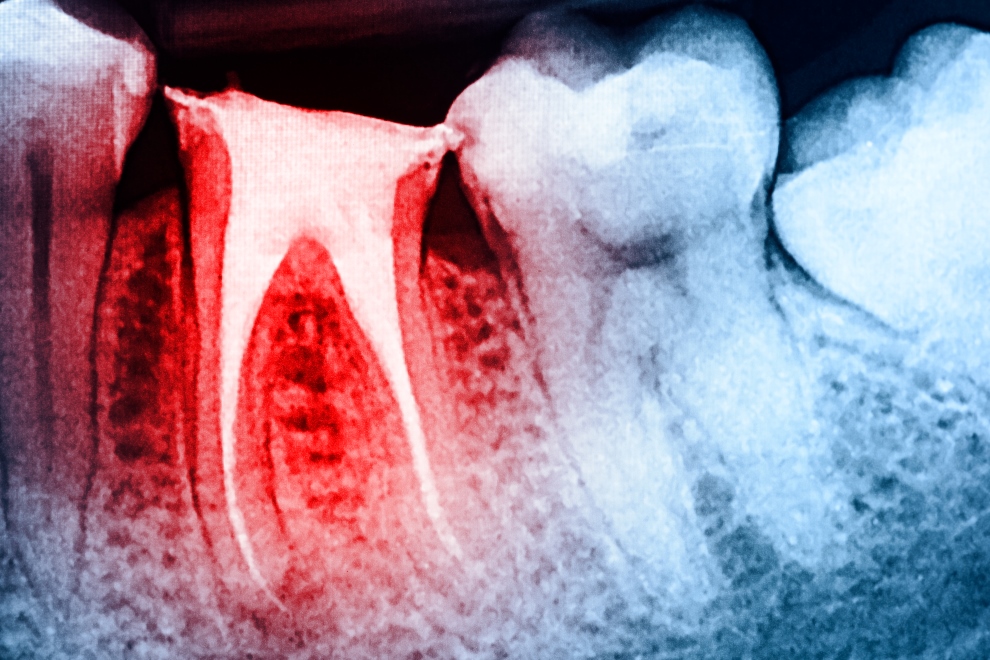

Es la rama de la Odontología que se encarga del tratamiento de la pulpa dental, es decir, la pulpa está compuesta por arterias, venas y nervios, por lo que ésta es la que le da la sensibilidad a los dientes. Cuando un  diente se ve atacado por una caries muy grande o por un golpe, la pulpa del diente, se ve alterada y empieza a provocar dolor en los dientes, por lo que es necesario retirar esa pulpa y colocar un material que se selle al 100% ese espacio que dejó la pulpa. Aquí encontrarás Cirujanos Dentistas que se encargan de realizar tratamientos de Endodoncia en las mejores condiciones.